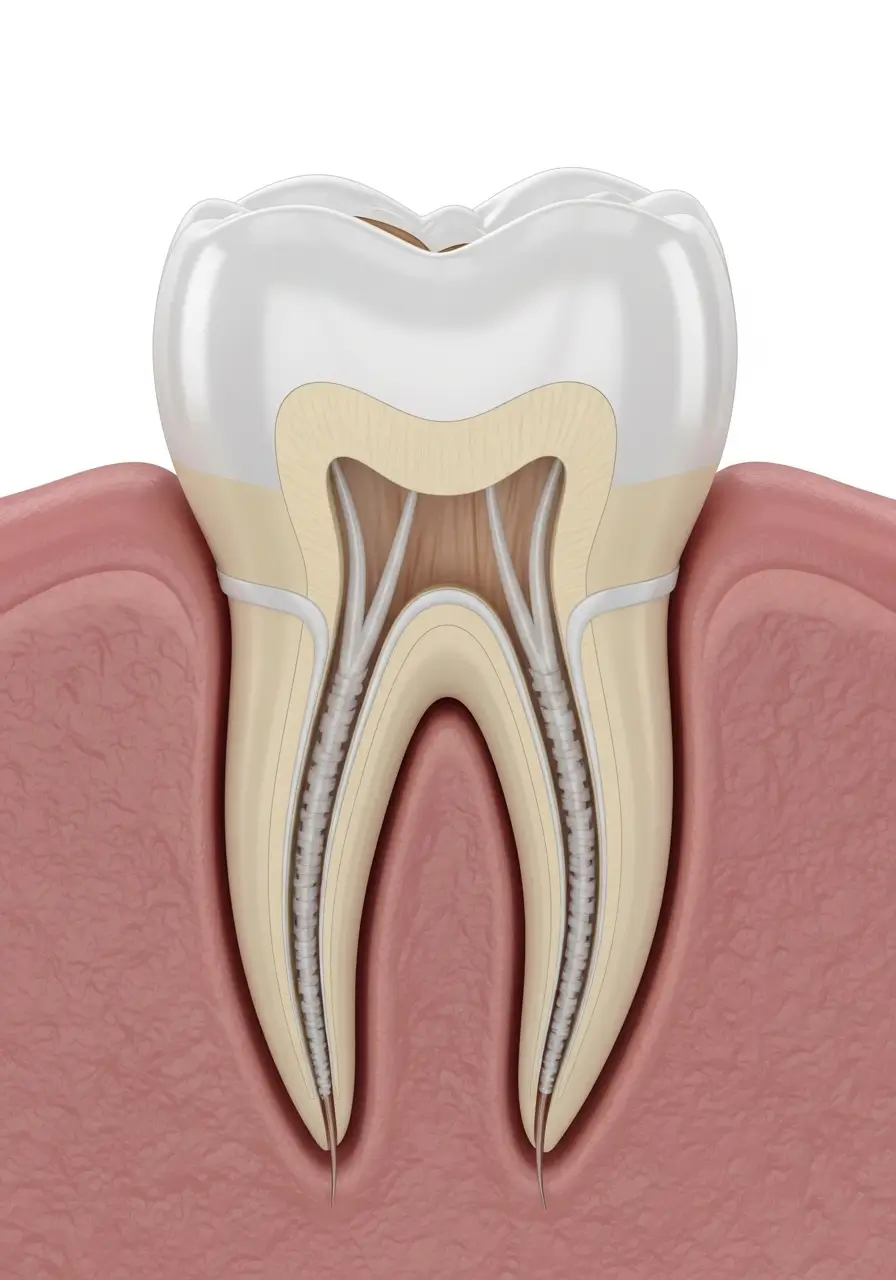

When the nerve or pulp inside a tooth becomes infected, root canal therapy may be needed to save it. Many people worry about this treatment, but with modern dentistry, root canals are gentle and effective. The process removes the infection, cleans the inside of the tooth, and seals it to prevent further issues. Root canal treatment in Sydney is often the best way to relieve tooth pain and keep your natural tooth, avoiding the need for extraction and replacement.

After a root canal, your tooth is usually strengthened with a crown or filling, allowing it to function just like a natural tooth. This makes root canal therapy not only a way to stop pain but also a long-term solution that helps preserve your smile and prevent more serious dental problems.

Root canal therapy—also called root canal treatment—removes infection from inside a tooth. It’s usually needed when decay or injury reaches the pulp, causing pain or risk of spreading infection. Root canal at our Bondi clinic, helps save your natural tooth instead of requiring extraction.

Thanks to modern techniques and local anaesthetic, root canal therapy is no more uncomfortable than having a filling. Most patients say the treatment actually relieves the pain caused by the infection, which would otherwise lead to tooth extractions.